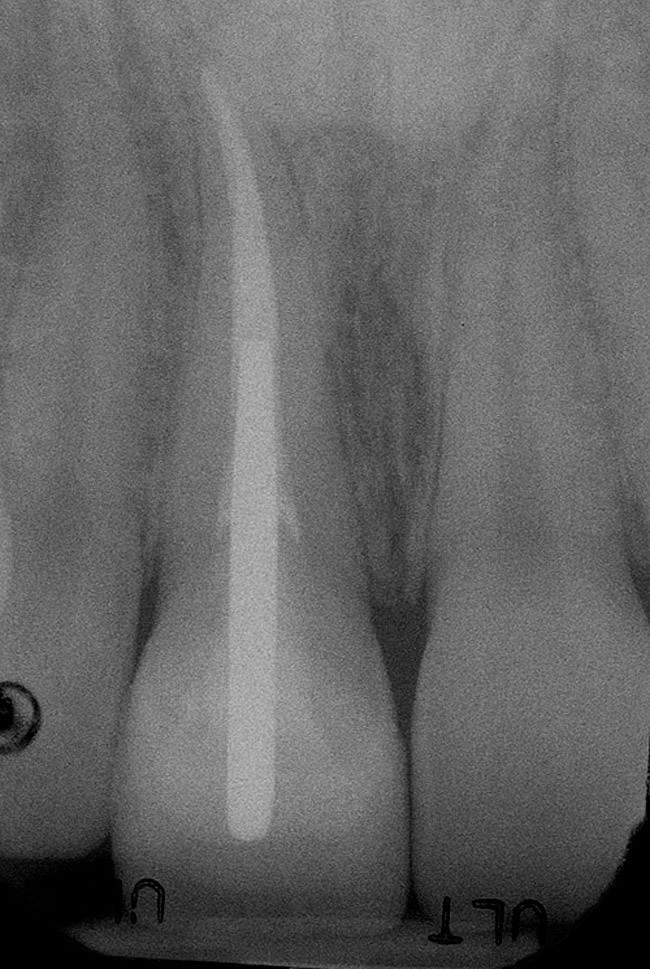

Figure 6a  Upper right central incisor, history of trauma, existing RCT and restoration unsatisfactory.

Figure 6a

Figure 6b  Upper right central incisor, history of trauma, existing RCT and restoration unsatisfactory.

Figure 6b

Figure 6c  Upper right central incisor, history of trauma, existing RCT and restoration unsatisfactory.

Figure 6c